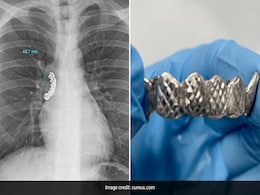

Man Gets Dentures Stuck In His Lungs After Accidentally Swallowing Them

- Sunday May 21, 2023

- World News | Edited by Ritu Singh

He was wearing a row of silver fake teeth when he had an epileptic seizure and accidentally swallowed them.